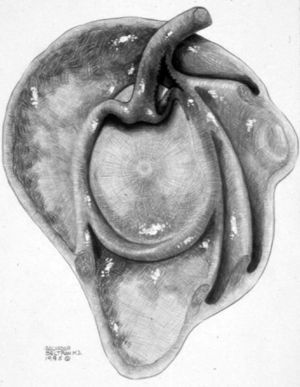

ALPSA (anterior labroliamentous periosteal avulsion)

Al igual que en el apartado anterior, existe también una separación de LG junto con la cápsula y el periostio, pero a diferencia de las lesiones de Bankart o Perthes, el LG se desplaza hacia dentro, por detrás del borde de la glenoides18 (fig. 12). La lesión de ALPSA puede cicatrizar por sinovialización (fig. 12), pero continúa siendo de carácter inestable.

Fig. 12.--ALPSA (anterior labroliamentous periosteal avulsion) agudo (A) y crónico (B). Nótese la separación del labio glenoideo y su desplazamiento posterior y medial por detrás del reborde glenoideo (flecha en A). En una fase crónica el labio glenoideo no se distingue como una estructura separada, sino como un engrosamiento de la unión entre el labio, la cápsula y el periostio (flecha en B).